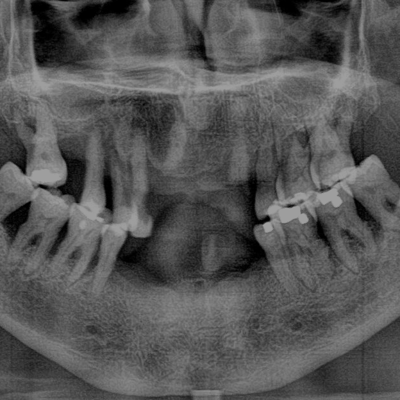

• Dental X-Ray Photo

• Panoramic Imaging for full-mouth diagnostics

• Digital X-Rays (faster results)